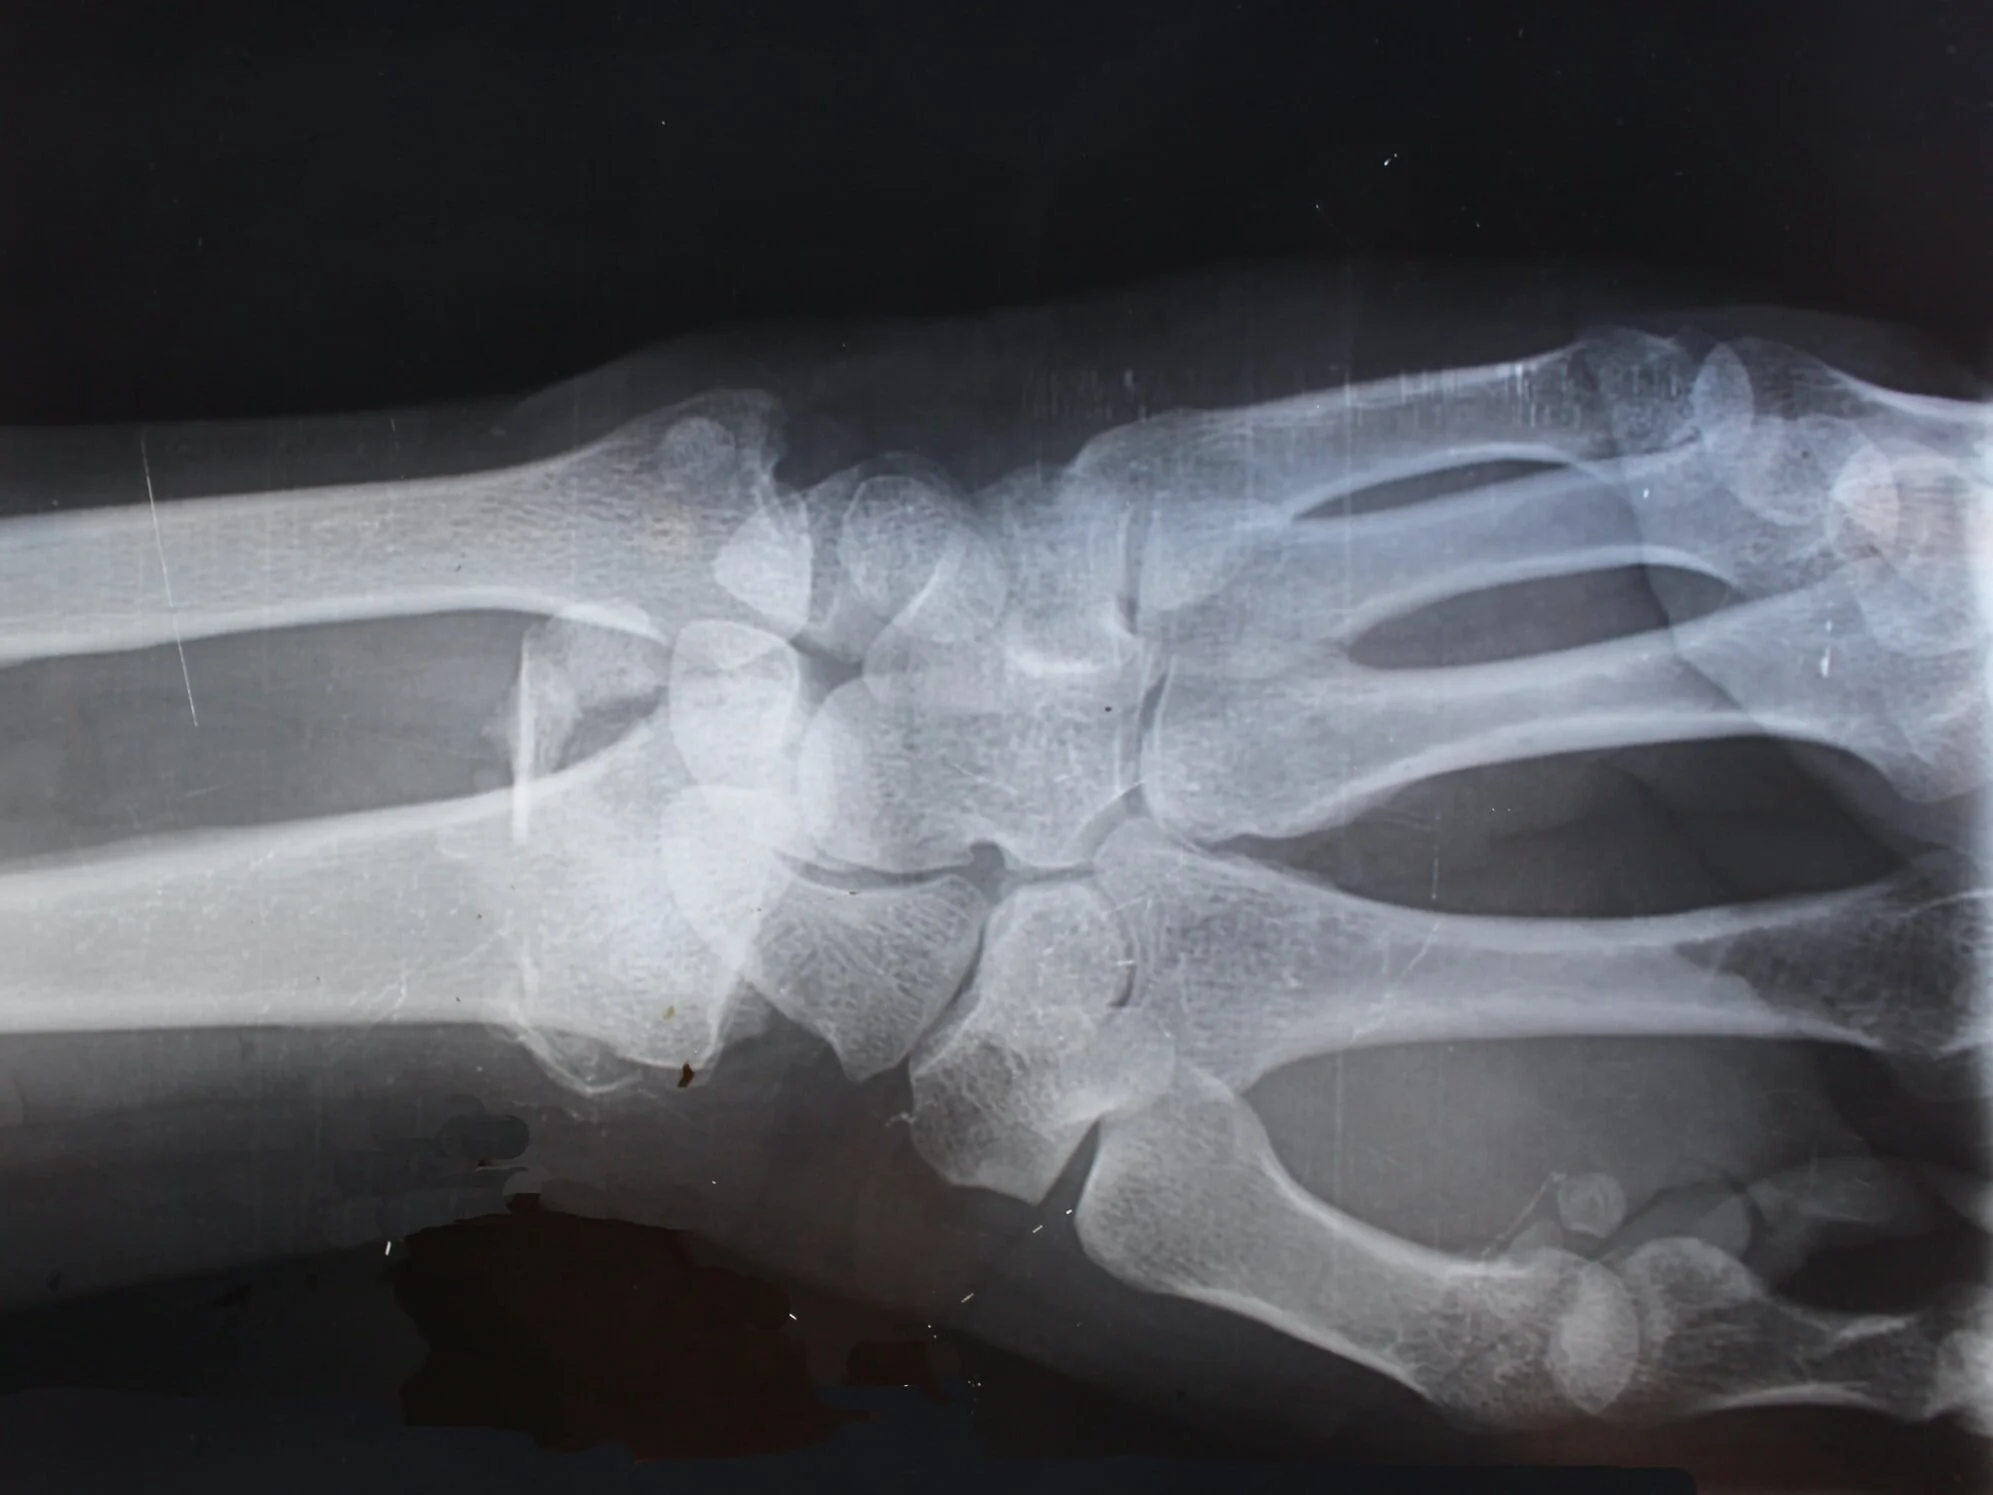

I turn to my six-year-old daughter, the one who’s been screaming, the one I’m annoyed with for disturbing my peace. She gingerly holds up her arm, tears of pain still streaming down her face.

I take one glance at that arm, and my frustration melts into compassion. There’s no blood, but I know enough anatomy to know bones aren’t meant to bend that way…